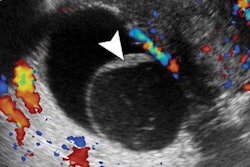

The team also wrote that they believe there is room to better prognosticate DCIS in the future by using MRI features. This is because of angiogenesis being an "important factor" for grading DCIS, which can be depicted only with MRI.